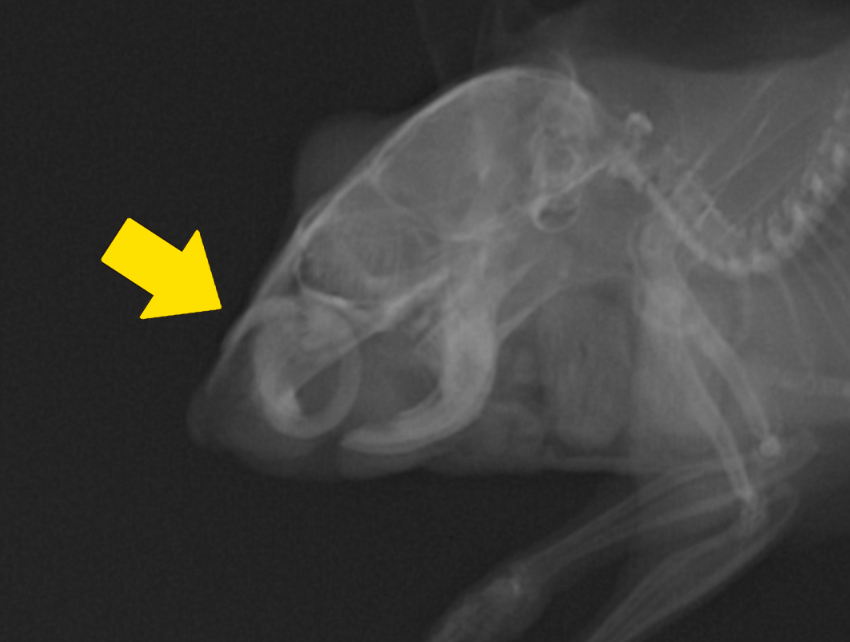

X線検査で確認すると、口腔内で1回転して顔面から飛び出しているのが分かります。

実は、これは切歯が伸びすぎて頬まで刺さってしまっている不正咬合の状態です。

不正咬合は、疼痛や食欲不振につながる場合があります。重度の場合は、このハムスターさんのように口の中で切歯が一回転して周辺組織に刺さることもあります。